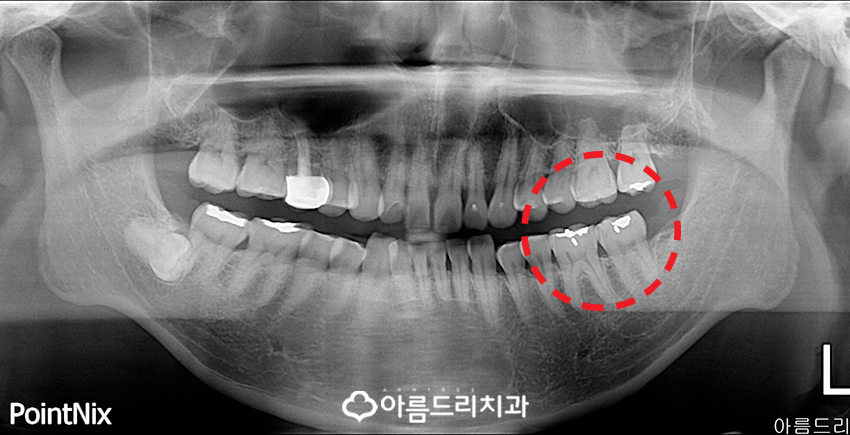

아름드리치과를 내원하신 환자분의 파노라마 X-ray사진을 보면 예전에 안쪽 어금니 부분이 조금 더 하얀색으로 군데 군데 뭔가 치료가 되어 있는 것을 확인 하실 수 있으실텐데요.

이 흔적은 과연 무엇일까요?

이것이 바로 예전에 깊지 않은 충치를 아말감 으로 치료를 하신 흔적이 남아있는 것이죠.

하지만 환자분께서는 예전에 어금니쪽 충치 치료를 깔끔하게 했는데 왜 다시 아픈건지 뭔가 잘못된것은 아닌지 궁금해하셨답니다.

보통 아말감을 이용한 충치치료의 경우 영구적이지 않기 때문에 사용하는 기간이 길어 짐에 따라 치아와 아말감간의 접착이 약해지는 문제로 인하여 그 사이(틈)에 2차적인 충치가 발생할 수 있는데 환자분도 그런 케이스였죠.